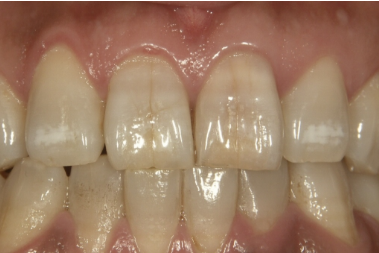

症例3

治療方法 ラミネートベニア法

治療期間 2ヶ月

治療費用 ラミネートベニア 1歯 ¥154,000×3 ¥462,000(税込)

治療の副作用.リスク 歯を削る必要がある

歯ぎしりや食いしばり癖があると欠けることがある

ラミネートベニア法

前歯の表面のヒビが目立つこと、前歯の先端の形がギザギザしている部分がお悩みでした。

前歯のヒビは、レジンの劣化により歯との境目に段差ができていることが原因です。

前歯の形と表面のヒビを完全にカバーして質感を整える場合はラミネートベニアがおすすめです。着色しにくく長期的に綺麗な状態を保つことができます。